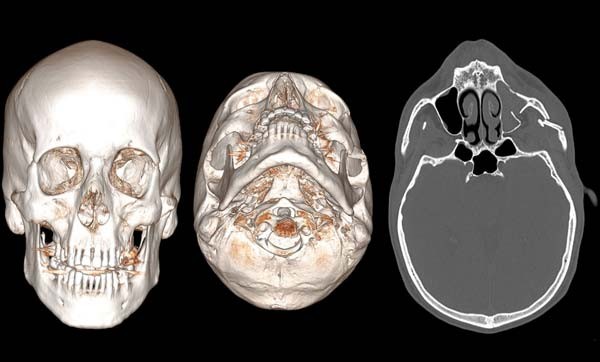

Un examen tomodensitométrique (TDM) du massif facial est demandé, qui met en évidence une fracture zygomatique gauche isolée (fig. 1).